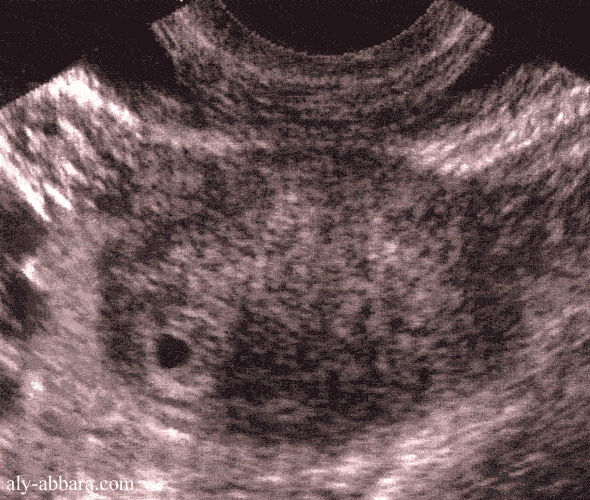

Grossesse extra-utérine dans la portion interstitielle de la trompe

(grossesse ectopique angulaire)